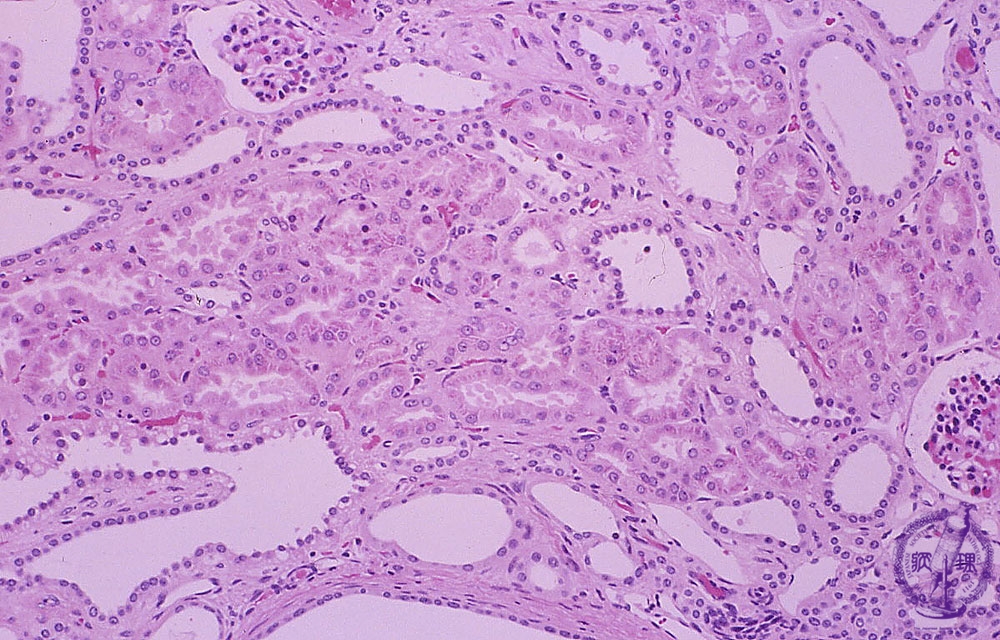

Microscopic view (H&E, low power, high power); All collecting tubules have irregular cylindrical dilation and cyst formation is observed